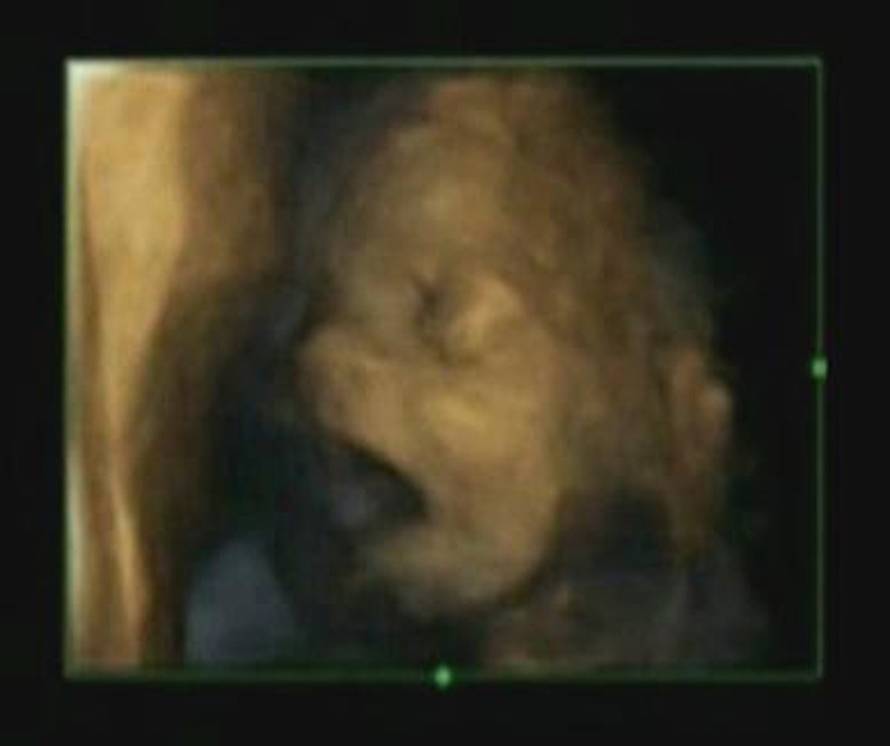

Prateći 15 zdravih fetusa, i dječaka i djevojčica, ustanovili su da bebe ne zijevaju iz istih razloga kao odrasli ljudi, već da se na taj način njihov mozak postupno razvija